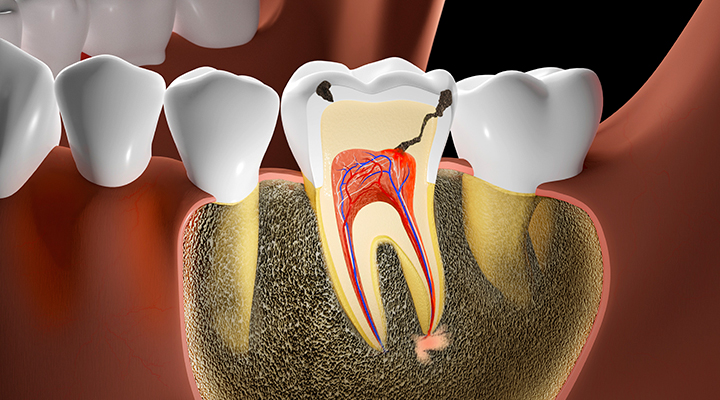

신경치료

치아를 살리는 신경치료

치아 내의 감염 조직과 혈관 등을 제거하고 깨끗이 소독한 후

특수한 재료로 밀봉하여 치아의 기능을 유지시키는 치료입니다.

충치/염증 확인

충치 혹은 외상으로 인하여 치아 신경에 염증이 발생됩니다.